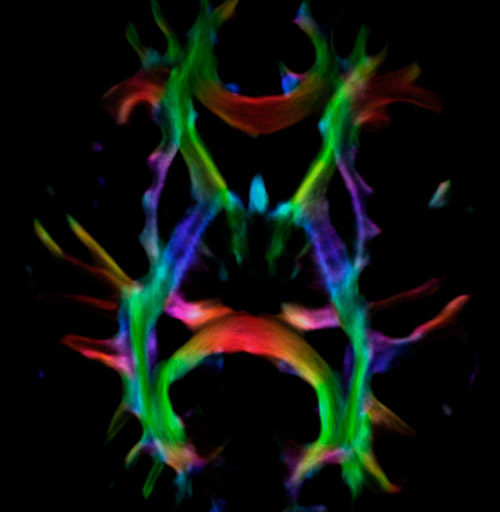

Fiber tracking from the left and right hippocampi to the fornix.

Fiber tracking from the left and right hippocampi to the fornix (green), and the corticospinal track based on a seed region of the posterior limb of the internal capsule.

All images were created from the same acquisition in a child using Ingenia 3.0T CX and 32-channel dS Head coil. Diffusion data was acquired at b-values 0, 500, 1000, 2000, 3000. The use of high b-values (3000 s/mm2) effectively suppresses extra-axonal water signal and provides high angular resolution.

Data processing was performed using open source software. Fiber tracking was performed using the MRtrix package (J-D Tournier, Brain Research Institute, Melbourne, Australia, https://github.com/MRtrix3/mrtrix3), Tournier et al. 2012. DEC TDI based on F Calamante et al 2010.